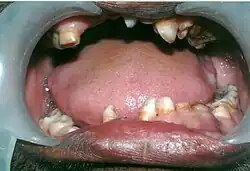

Mouth showing many over-retained deciduous teeth and some missing teeth.

- The permanent teeth include supernumerary teeth. Unless these supernumeraries are removed they will crowd the adult teeth in what already may be an underdeveloped jaw. If so, the supernumeraries will probably need to be removed to make space for the adult teeth. Up to 13 supernumerary teeth have been observed. Teeth may also be displaced. Cementum formation may be deficient.[13]

- Failure of eruption of permanent teeth.